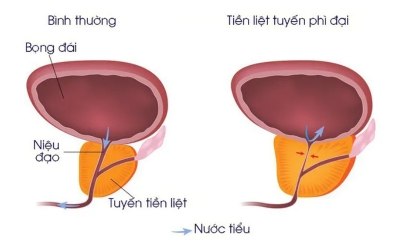

3. Tăng Cường Sinh Lý Và Sức Khỏe Sinh Sản

Một trong những lợi ích của Cordyceps Sinensis với sinh lý là khả năng tăng cường sinh lực và hỗ trợ sức khỏe sinh sản. Đối với nam giới, Cordyceps Sinensis giúp cải thiện chức năng thận, tăng cường sức mạnh và khả năng tình dục tự nhiên. Điều này là nhờ vào tác dụng kích thích tuần hoàn máu và sản xuất hormone sinh dục.

- Cordyceps Sinensis tăng cường sinh lý: Cordyceps Sinensis giúp nam giới cải thiện sinh lực, giảm thiểu tình trạng mệt mỏi và tăng cường năng lượng.

- Hỗ trợ sinh sản: Loại thảo dược này còn có thể cải thiện chất lượng tinh trùng, giúp nâng cao khả năng sinh sản.